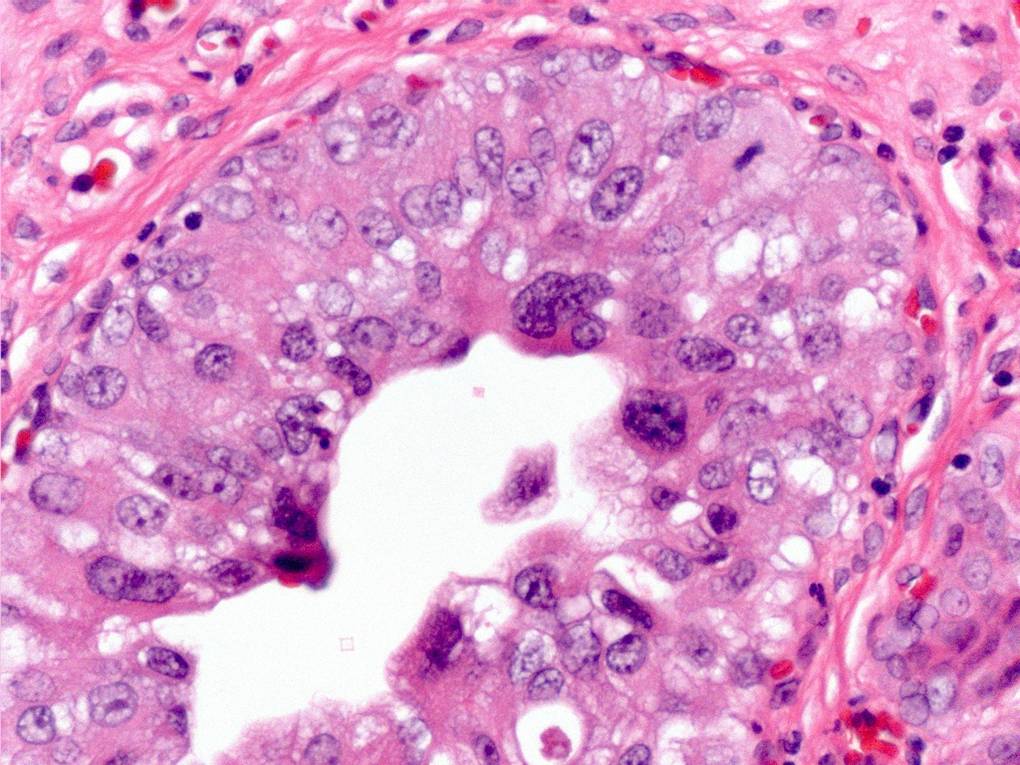

Bladder Flat Lesions

Case ID: 145